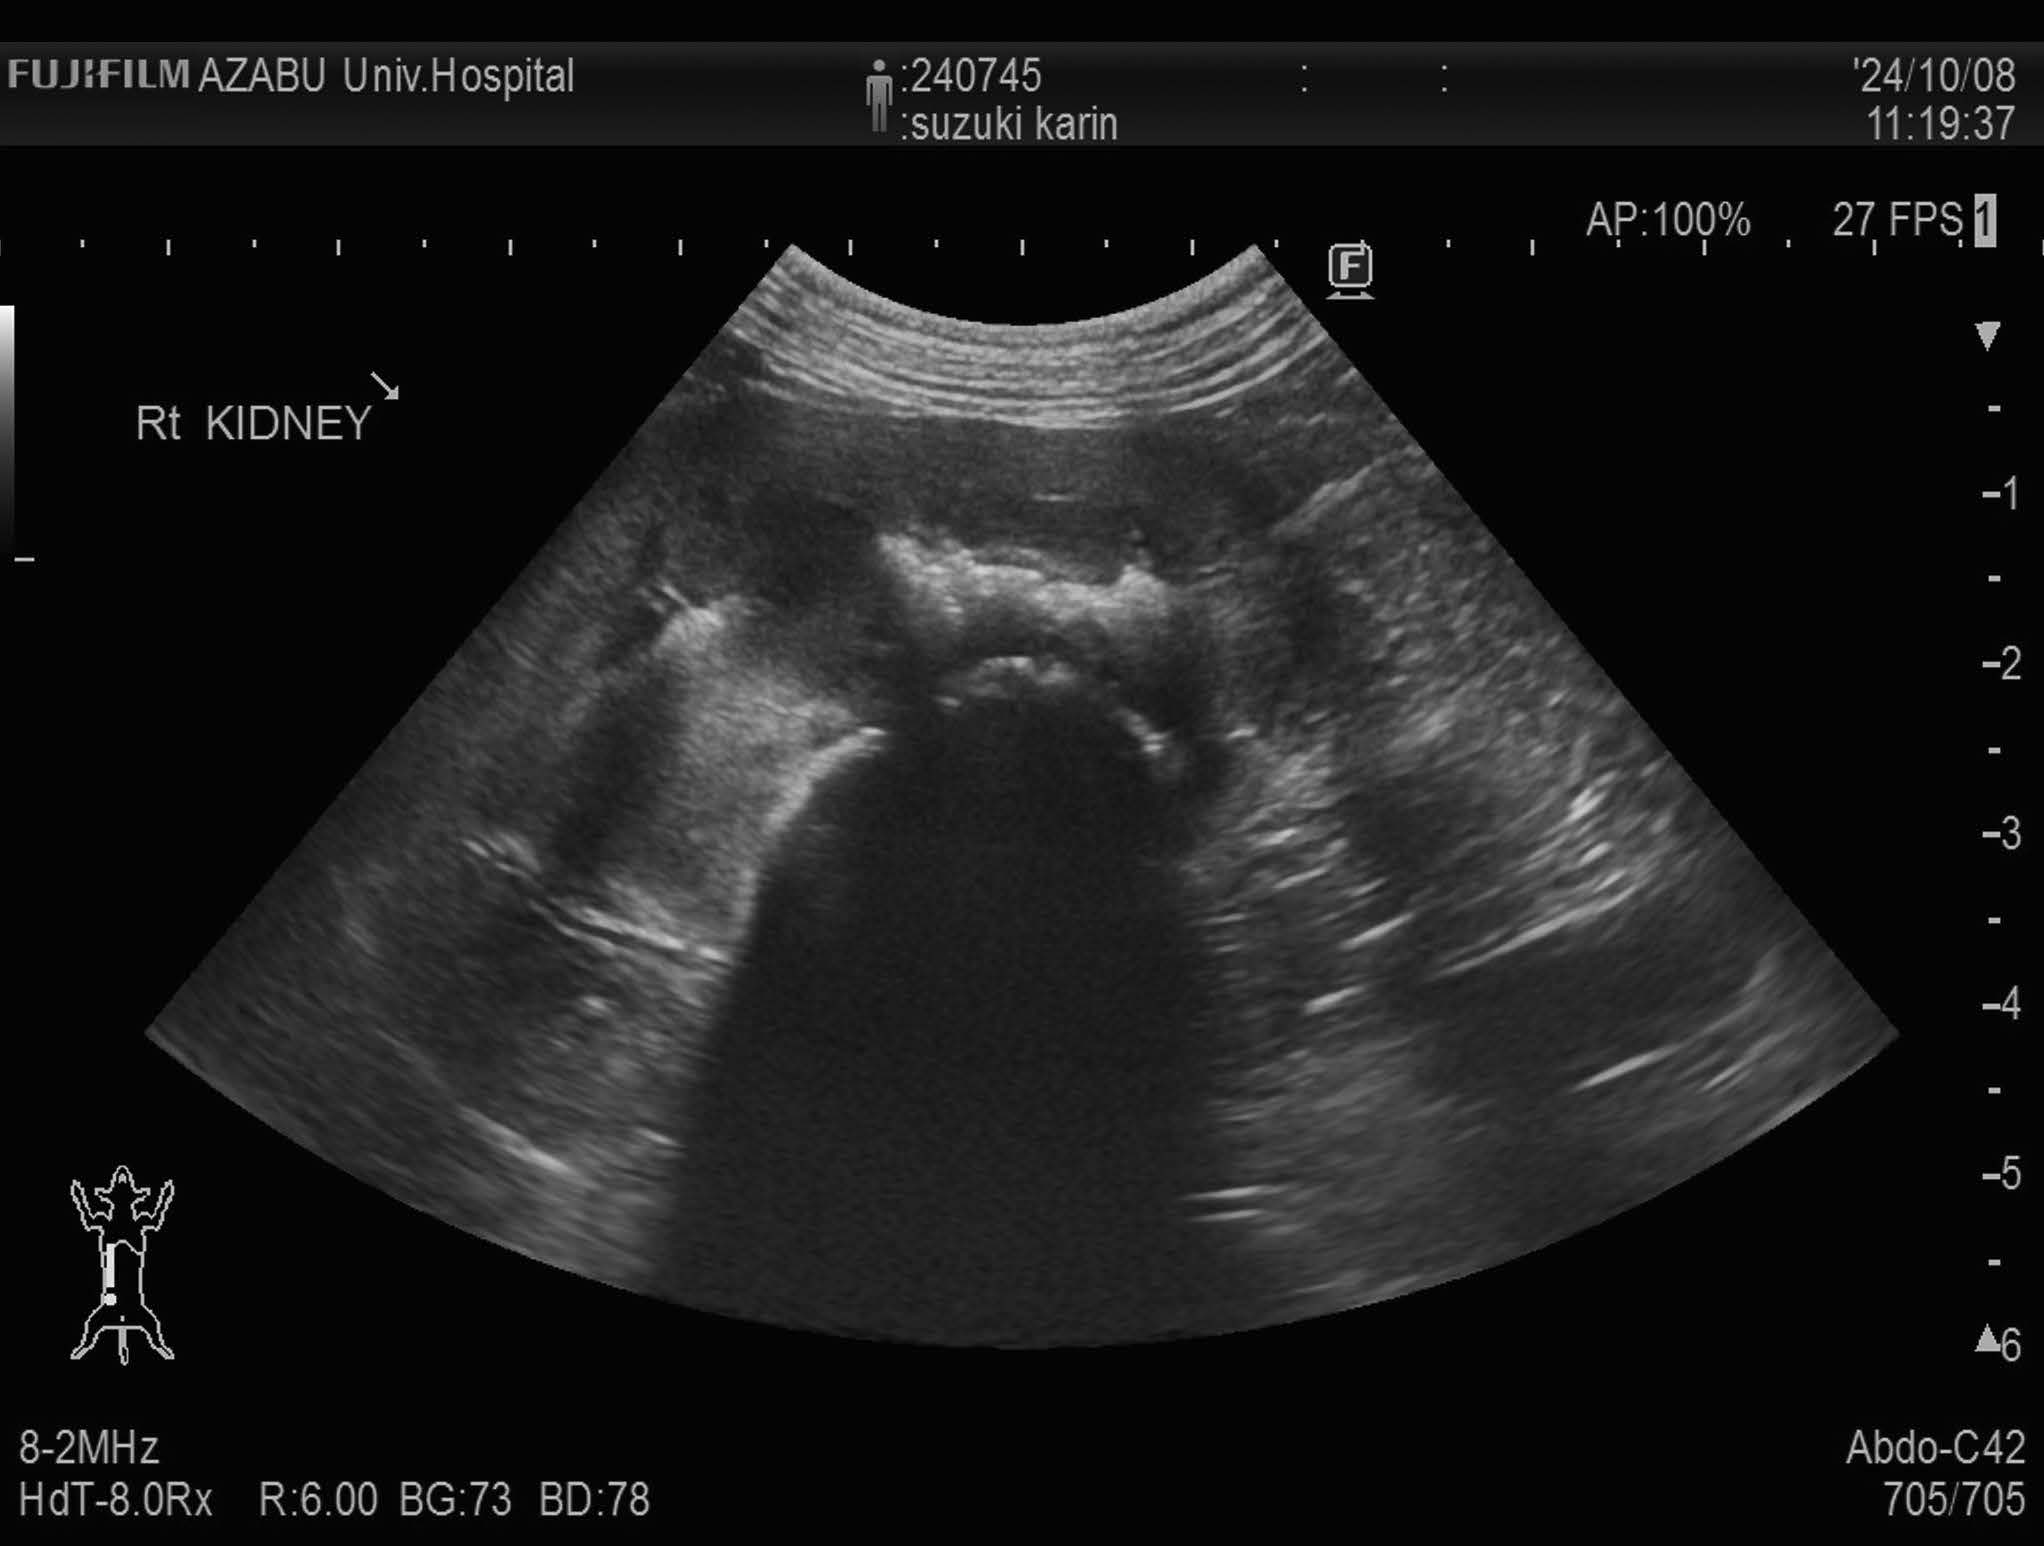

画像検査:腹部X 線検査では,肝サイズの低下と両腎にX 線不透過性の低い陰影が認められた(図1).腹部超音波検査では両側腎盂領域において,音響陰影を呈する高エコー構造物を認めた(図2).膀胱内には,高エコー源性の浮遊物及び沈渣が観察された.

図1 腹部X 線画像(仰臥位)

両側腎臓に軟部組織よりもわずかに不透過性が高い陰影を認める.